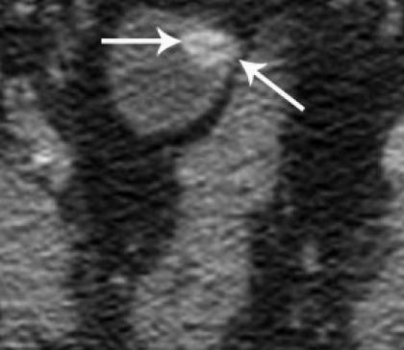

Hình 33: Hình ảnh carcinoid trong túi thừa Meckel bắt thuốc cản quang mạnh (mũi tên).

(Scott R. Paulsen et al (2006). CT Enterography as a Diagnostic Tool in Evaluating Small Bowel Disorders: Review of Clinical Experience with over 700 Cases. RadioGraphics; 26:651).